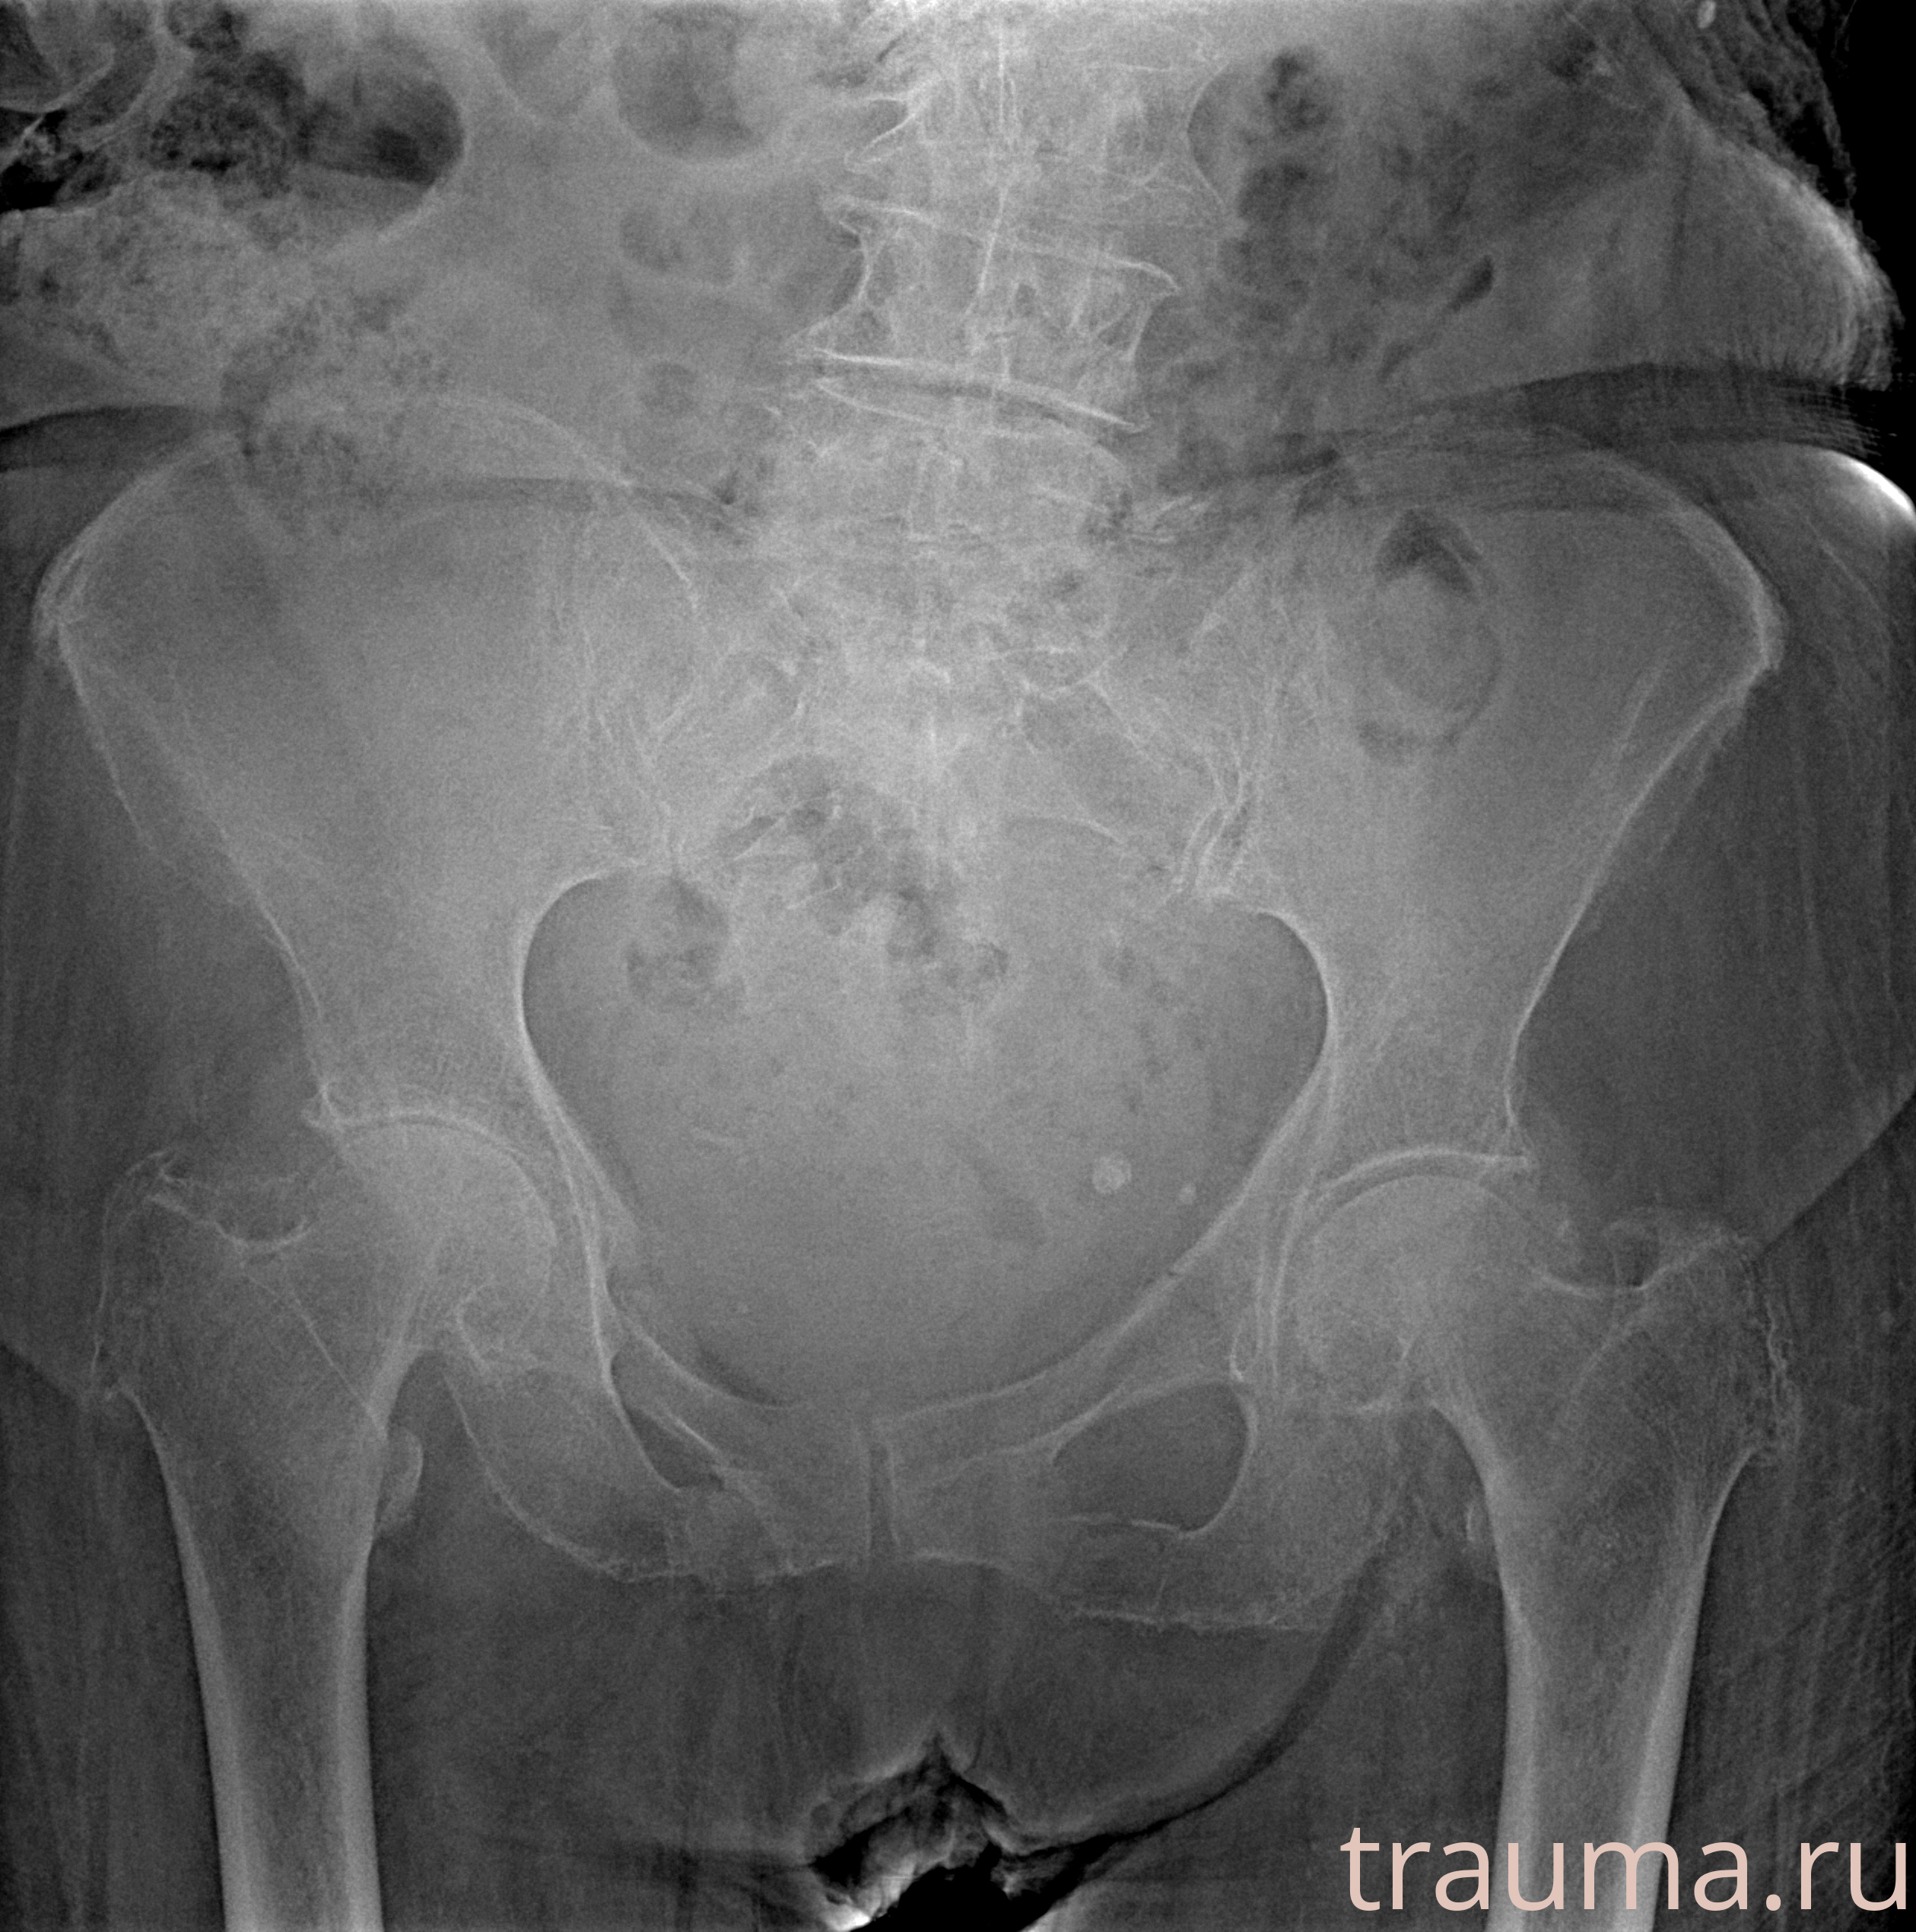

Рентген на дому: по вашему адресу приезжает врач-рентгенолог, травматолог-ортопед с мобильным рентгеновским аппаратом, проводит диагностику травмы или заболевания, делает необходимые рентгенограммы, дает рекомендации по дальнейшему лечению. Получить качественные снимки в домашних условиях возможно благодаря уникальной методике, разработанной МосРентген Центром для института  Склифосовского